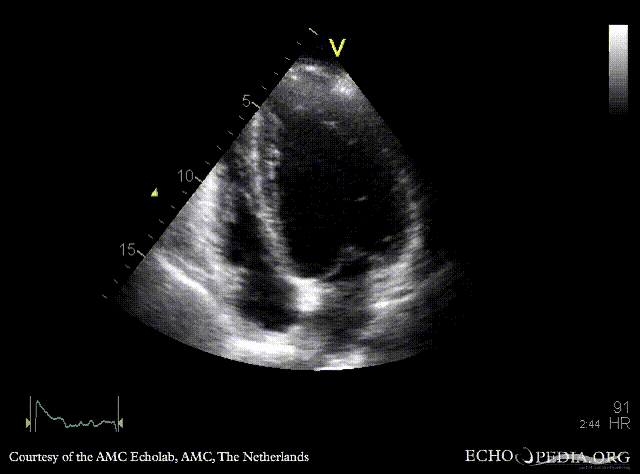

A4CH: dilated left ventricle A5CH: vegetations on aortic valve, dilated left ventricle